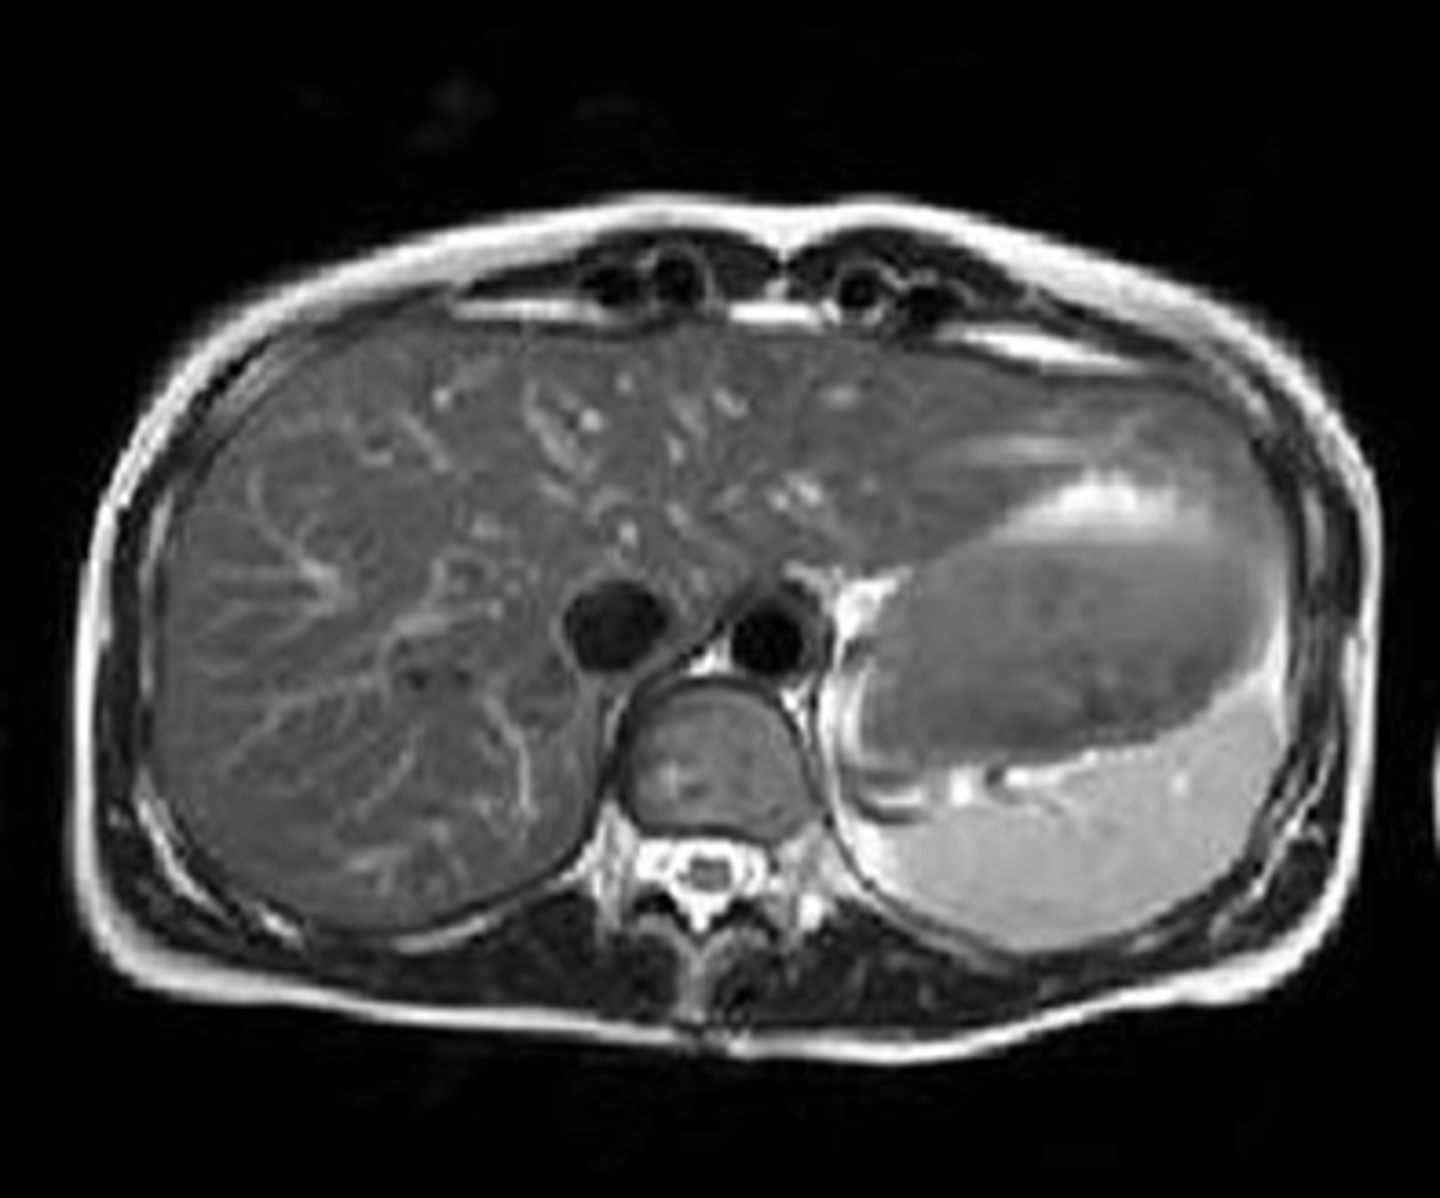

Normal